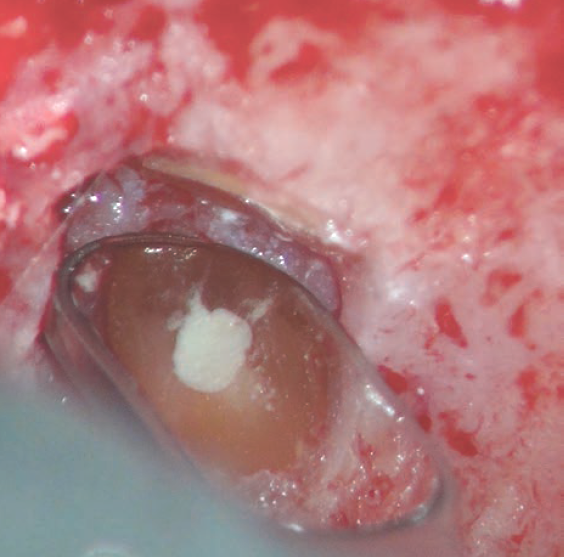

什么是显微镜手术什么是显微根尖囊肿手术?_https://www.jmylbn.com_新闻资讯_第3张

图2  根尖区放大后的影像,用显微口镜看根尖倒充是否达标